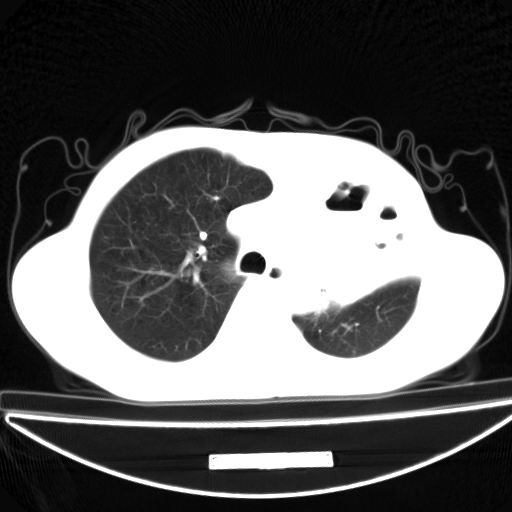

以下是引用杀毒软件在2009-4-28 17:58:00的发言:[br]考虑----左肺慢性肺脓肿形成继发上叶含气不良---抗炎后复查---待排肿瘤所致[br][br][本贴已被 杀毒软件 于 2009-4-28 18:01:26 修改过]